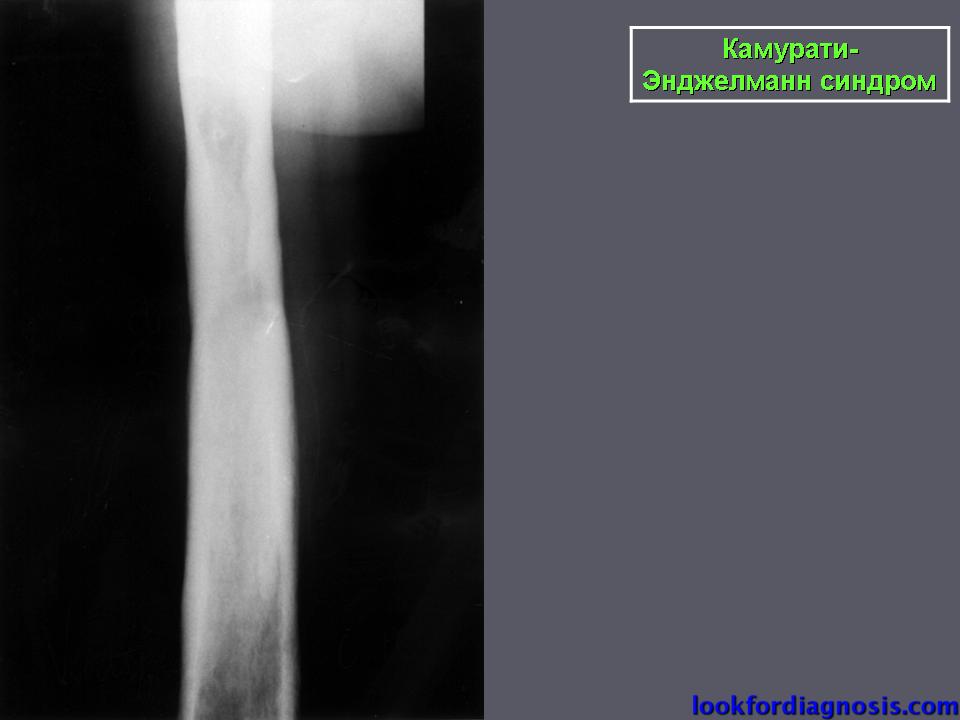

При генерализованном гиперостозе происходит нарушение периостального и эностального костеобразования в энхондрально преформированных костях, в результате чего в них развиваются периостозы и эностозы. Это врожденное семейно-наследственное заболевание скелета подробно изучено только благодаря рентгенологическим исследованиям. Впервые его описали F. Camurati (1922) и G. Engelmann (1929), а из отечественных авторов — Д. Г. Рохлин и М. А. Финкельштейн (1940), которые наблюдали семью, у членов которых в двух поколениях имелись изменения в скелете.

Патологические сдвиги в остеогенезе возникают в постнатальном периоде, в первые годы жизни, клинически не проявляются, но медленно и неуклонно нарастают, продолжаясь и по окончании роста и формирования скелета. У взрослого иногда возникают периодические боли в костях, чувство тяжести в ногах, скованность в движениях, могут прощупываться утолщения костей. Патологических переломов, искривлений или каких-либо, других деформаций не возникает. Изменения в крови отсутствуют. Сдвигов биохимических показателей не выявлено. При этой разновидности костной дисплазии усилена остеобластическая функция надкостницы, что вызывает постепенное утолщение коркового слоя снаружи за счет напластования на его поверхности новых костных слоев. Вследствие этого корковый слой в отдельных местах и в разные периоды представляется разволокненным, а затем приобретает однородную гомогенную структуру. Наружная поверхность его остается гладкой или несколько волнистой.

Утолщаются те отделы скелета, которые развиваются при участии надкостницы. Этот процесс усиливается в те возрастные периоды, когда наиболее бурно происходит рост скелета. Активность надкостницы сохраняется и по окончании его роста, утолщение костей продолжается у взрослых. Выраженность утолщения зависит от степени функциональной активности надкостницы отдельных костей. Соответственно этому больше всего (иногда почти в 2 раза) утолщаются диафизы длинных трубчатых костей. Вследствие этого эпифизы по сравнению с громоздкими диафизами кажутся как бы уменьшенными в размерах. Так же утолщаются диафизы пястных и плюсневых костей, меньше — основные фаланги, еще меньше — средние, а ногтевые совсем не изменяются.

Наряду с повышением активности надкостницы, создающей костную ткань на наружной поверхности коркового слоя, замедляется резорбция его изнутри, вследствие чего корковый слой утолщается в обе стороны. Однако это происходит не на всем его протяжении, а лишь местами. Супраспонгиозный слой не имеет четких границ и незаметно сливается с губчатой структурой эпифизов и метафизов, а утолщаясь на уровне костномозгового капала в его сторону, вызывает неравномерное, иногда очень значительное сужение канала.

Рентгенологическая картина генерализованного гиперостоза при исследовании всего скелета очень характерна, поэтому нет необходимости в дифференциальной диагностике, но рентгенологически выявленные локальные изменении могут быть ошибочно истолкованы. Например, изменения, обнаруженные в позвоночнике или ребрах, могут быть приняты за гемангиому, а в длинных трубчатых костях — за проявления болезни Педжета.